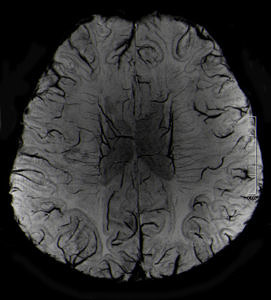

Der neue MRT ermöglicht dank der sehr hohen Auflösung detaillierte Einblicke in den menschlichen Bewegungsapparat, zeigt präzise die Stoffwechselprozesse im Gehirn und hilft außerdem bei der Darstellung neurologischer Krankheiten.

Bei 7-Tesla sind Gehirnschädigungen dank der besseren Auflösung und des deutlich stärkeren Bildkontrasts viel klarer zu erkennen. Viele Erkrankungen können so wahrscheinlich besser und schneller erkannt und damit effektiver behandelt werden.

Anwendungsbeispiele hierfür seien Multiple Sklerose, Hirntumoren oder Metastasen, Epilepsie und Demenz, bei denen die höhere Detailauflösung neue diagnostische Möglichkeiten bietet, die bei niedrigeren Feldstärken so nicht möglich wären.

Der Grund für die bessere Auflösung der Untersuchungsbilder ist die höhere Messgenauigkeit des neuen Systems. Diese hängt mit der Feldstärke des Magneten im MRT zusammen. Je stärker das Magnetfeld ist, desto genauer ist die Bildgebung. Da die Feldstärke am 7-Tesla-MRT mehr als doppelt so hoch ist wie die der heute gebräuchlichen 3-Tesla-MRT, können nicht nur feinste Gewebestrukturen besser sichtbar gemacht werden, sondern auch Stoffwechselprozesse im Gewebe. Am Standort Erlangen werden die Möglichkeiten des neuen Ultrahochfeld-MRT jetzt intensiv weiter erforscht.